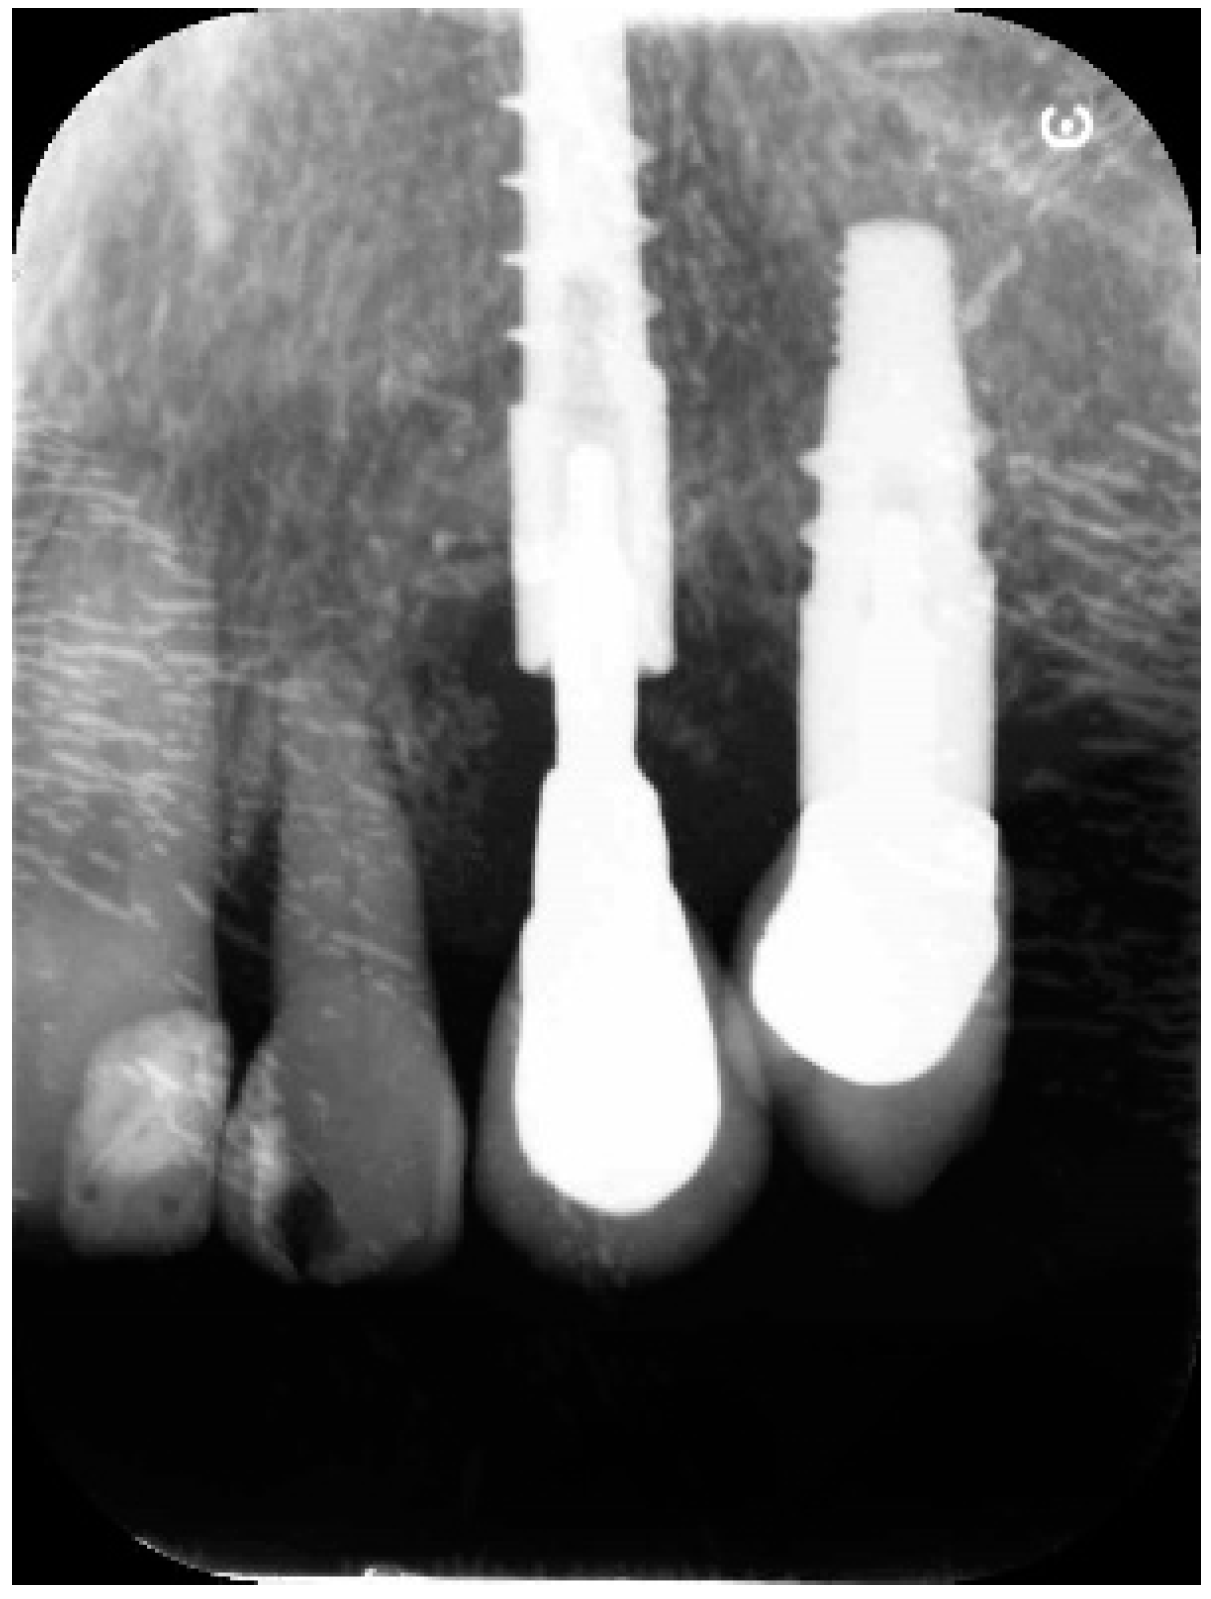

2. Results

4.1. Surgical Procedure for Open Flap Debridement

4.2. Clinical Case